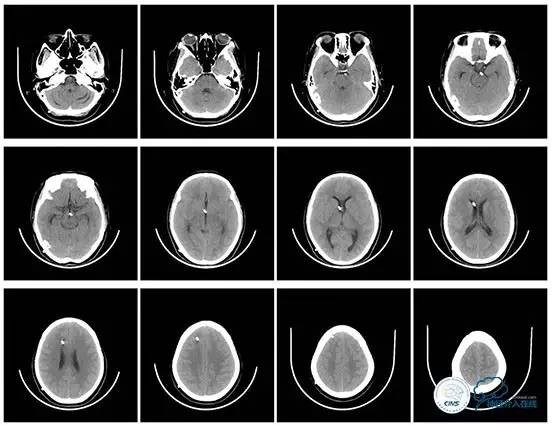

术后头颅CT

术后即刻患者头痛缓解。

停用脱水药,次日腰穿压力160mmH2O。

术后2月,患者门诊复查,诉头痛缓解、无癫痫发作、无脑脊液鼻漏及发热。

复查头颅及颞骨CT未见明显异常。

头颅CT(2017.6.20)

颞骨CT(2017.6.20)